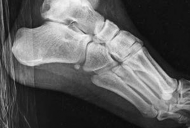

Standard orthogonal radiographs (anteroposterior and lateral) are sufficient for initial diagnosis, but they routinely underestimate the complexity of partial articular fractures. A high-resolution computed tomography (CT) scan with two-dimensional multiplanar reformats (coronal and sagittal) and three-dimensional surface rendering is considered the standard of care.

CT imaging is critical for:

1. Identifying the exact location and size of the articular fragments.

2. Detecting central articular depression that is obscured by the cortical rim on plain films.

3. Mapping fracture lines extending into the diaphysis.

4. Planning the surgical approach to ensure direct access to the primary fracture line.